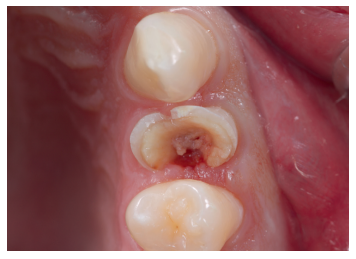

Una vez se hubo posicionado el diente 2 mm supragingival, se procedió a la ferulización con alambre de acero a los dientes adyacentes (Figuras 3 y 4) y la eliminación de cualquier tipo de oclusión, utilizando topes oclusales en los segundos molares inferiores. La ferulización se mantuvo durante dos semanas, coincidiendo con el momento de la endodoncia (Figura 5). El paciente fue citado para las revisiones periódicas y posteriormente para la rehabilitación del diente, una vez hubieron concurrido 6 semanas desde la extrusión, en las que se haya obtenido una cicatrización de los tejidos de soporte supracrestales10. En este momento, tras comprobar signos clínicos, periodontales y radiográficos saludables, se citó al paciente para el tallado y la confección mediante flujo digital (Cerec® System) de una endocorona de disilicato de litio (e.max®, Ivoclar Vivadent). El acondicionamiento de la corona se realizó con ácido fluorhídrico y silano, y para la cementación se utilizó cemento de resina (Calibra®, Dentsply Sirona).

Las revisiones se realizaron de forma periódica hasta los 12 meses de seguimiento (Figuras 6 y 7), observando en todas ellas signos clínicos saludables. El paciente no presentó reabsorción radicular, anquilosis, ni problema periodontal en los exámenes radiográficos que se realizaron desde el diagnóstico hasta el año (Figuras 8 -12); y la ganancia de ferrule obtenida de 2mm se mantuvo estable.